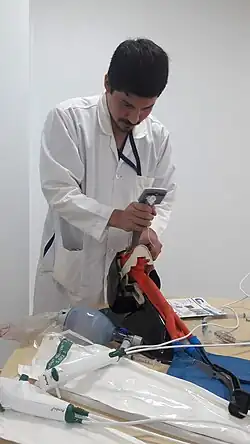

Opérateur

Il doit être formé à la technique, il peut s'agir d'un médecin, d'un inhalothérapeute, d'un infirmier (en France, il doit être infirmier anesthésiste diplômé d'état) ou d'un paramedic. Il doit respecter les règles d'hygiène (lavage des mains, utilisation de matériel décontaminé) et être protégé contre les risques de contamination provenant du patient (port de gants, de lunettes et de masque protecteur). Il est placé derrière la tête du patient, il peut être debout (aux urgences et au bloc opératoire), assis ou allongé (en préhospitalier).

Apprentissage de l'intubation

- Tous les praticiens susceptibles de réaliser une intubation (urgentistes) doivent se former aux techniques recommandées[15].

- La formation par simple compagnonnage ne doit pas débuter sur le patient mais doit commencer par un apprentissage sur mannequin pour passer ensuite à un apprentissage sur le patient. En effet l'apprentissage sur mannequin permet une réalisation du geste sans entraîner de risque pour le patient. Certains mannequins sont munis de capteurs permettant d'alerter en cas de risque de traumatismes dentaires et reproduisent l'anatomie normale de façon fidèle. Malgré leur réalisme, la reproduction des conditions réelles n'est à ce jour qu'approximative.

- L'apprentissage au bloc opératoire, une fois la pratique sur mannequin acquise, permet de poursuivre la maîtrise de la technique, dans des conditions d'encadrement et de sécurité optimales. L'obtention d'un diplôme de médecine d'urgence (CAMU en France) nécessite d'ailleurs un stage au bloc opératoire.